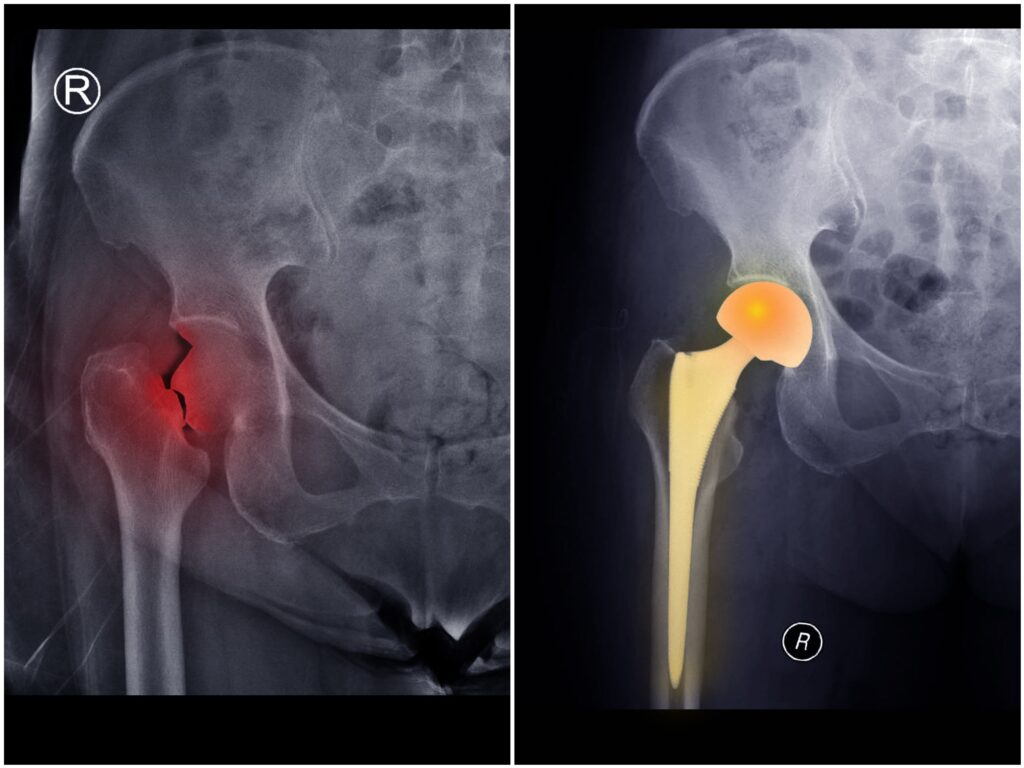

Partial Hip Replacement, also known as Bipolar Hemiarthroplasty, is a commonly performed and effective surgical procedure primarily used to treat hip fractures, especially in elderly patients. Dr. Manal Gore provides expert bipolar hip replacement surgery focused on restoring mobility safely and minimizing long-term complications.

In this procedure, the damaged ball (head of the femur) is replaced while preserving the natural hip socket. This approach allows smoother joint movement and supports faster rehabilitation.